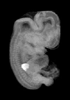

Carnegie Stage 19 (47 post-ovulatory days)

Most embryos at stage 19 are approximately 47-48 post-ovulatory days old and measure 17-20 mm in length. Distinguishing criteria for this stage include straightening of the trunk, the limbs extend nearly directly forward, toe rays are prominent, but interdigital notches have not yet appeared in the foot.

MRI Slice Selector

Mouse: click on a line below to select a view

Finger: tap a line below with a very light touch